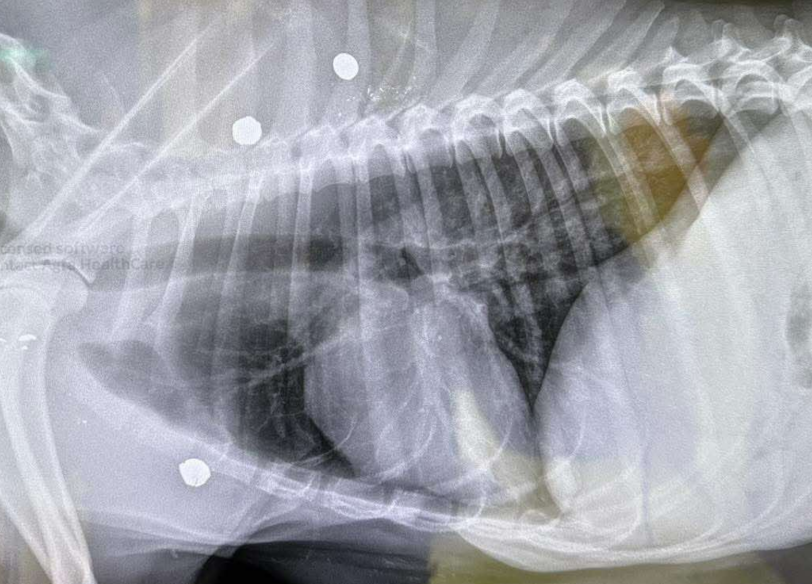

One bullet went through the dog, and X-rays showed three more are still inside her body, but they did not hit any vital organs.

“At this point, we are hoping we won’t have to operate that those will stabilize where they are, but one grazed the shoulder blade, causing bone fragments to travel,” said Kent. “There was one in the back that came straight through the skin and out the other side and two more back in the shoulder. So, she took several direct hits.”